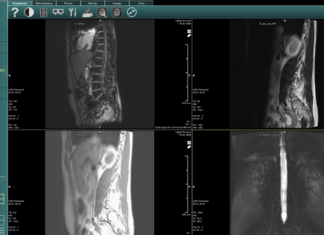

MRT-Aufnahmen mit Wine öffnen

MRT-Aufnahmen werden leider in einem gesonderten Format abgespeichert. Wenn man eine entsprechende CD ausgehändigt bekommt, wird man schnell feststellen, dass man die Bilder auf...